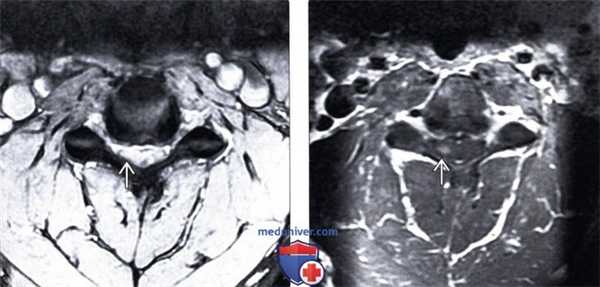

(Слева) На аксиальном T2*GRE МР-И видны признаки умеренно выраженного фораминального стеноза на фоне относительно легких дегенеративных изменений дугоотростчатых суставов и гипертрофии унковертебральных суставов. Спинной мозг с признаками усиления сигнала вследствие хронического сдавления и миеломаляции.

(Справа) Т1-ВИ с КУ: признаки фораминального стеноза вследствие гипертрофии унковертебральных суставов и дегенеративных изменений дугоотростчатых суставов, в толще спинного мозга виден очаг усиления сигнала, представляющий собой зону миеломаляции.